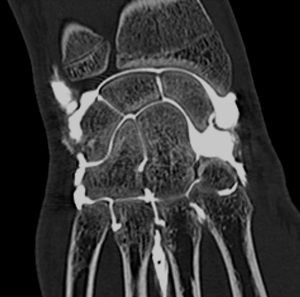

Компьютерная томограмма кисти руки.

На серии КТ снимков лучезапястного сустава визуализируются кости, мышцы, связки и сухожилия запястья в нескольких плоскостях. В ходе расшифровки оценивается состояние мягких тканей, костных структур, определяется суставная щель исследуемого сустава. Определяются признаки патологических изменений – истончение суставных хрящей, склероз замыкательных пластинок, кисты, деминерализация костной ткани, деформация и сужение суставной щели, опухоли и образования, трещины и переломы, участки некроза или воспаления костной ткани. При необходимости выполняется трехмерная реконструкция области лучезапястного сустава.